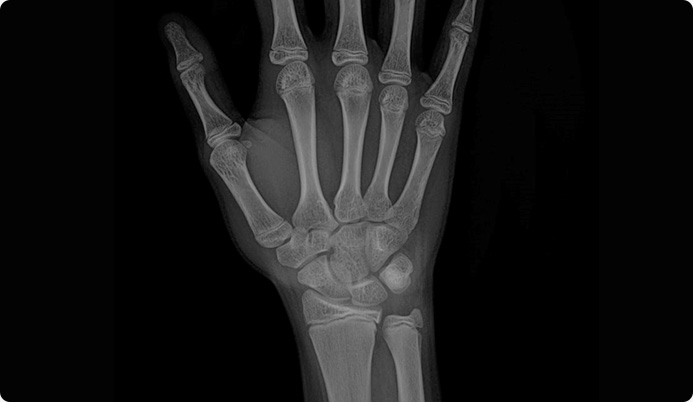

삼각섬유연골복합체 파열이 있을 경우 MRI 에서 다음과 같이 뼈 부착부에서의 파열(빨간 원)과

관절액이 원위요척관절로 새어 나온 이차적인 변화(노란 원)이 관찰됩니다.